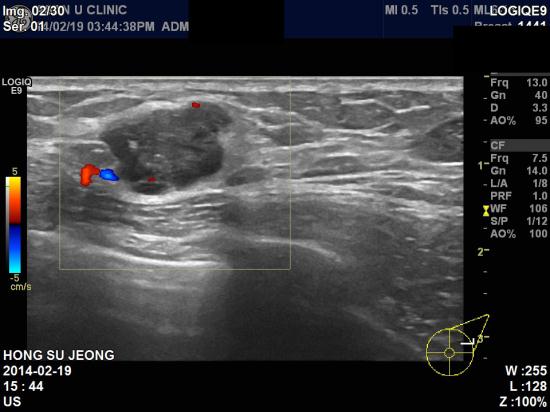

아산유외과 개원 후 66번째 유방암 진단.

한달전부터 좌측유방에 만져지는 멍우리와

통증을 주소로 내원하신 51세여자분이십니다.

본원 초음파 검사결과 좌측유방 2 : 30분방향에 1.61 cm 의 결절소견과

좌측겨드랑이의 림프절 비대소견있어

각각 조직검사결과 침윤성유관암 및 겨드랑이 림프절 전이로 진단되었습니다.

유방암 발병률이 높은 40~50대에는 건강검진을 챙겨서 하셔야하고

만져지는 종괴가 있을경우에는 반드시 전문의의 진찰이 필요합니다.

환자분의 빠른쾌유를 기도합니다.